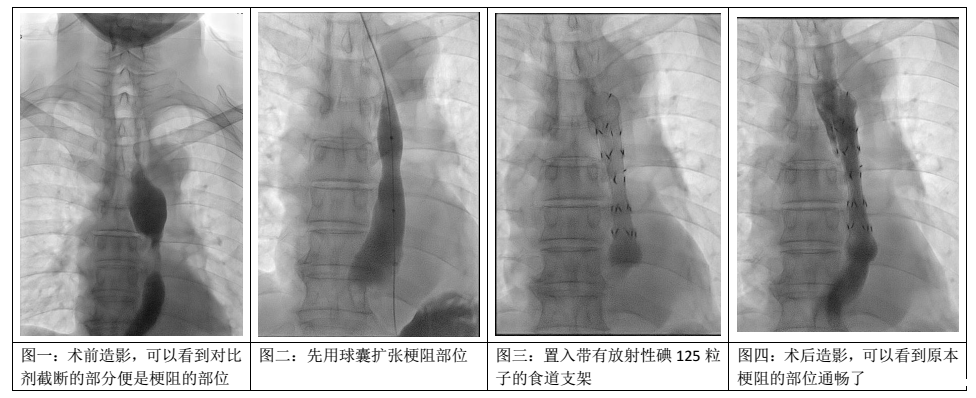

后来老姜经人介绍到了我院介入血管科,终于解决了他吃饭的难题。经多学科讨论同意后,介入血管科何旭主任为老姜做了我院第一例食道碘粒子支架置入术,这种介入治疗方法既可以解除了食道狭窄,又能通过局部内照射的方式来控制肿瘤进展。

以下是手术过程,整个手术不到5分钟: